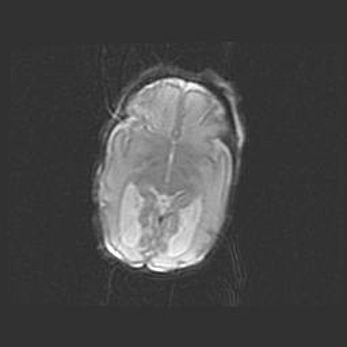

Подострая гематома правой гемисферы мозжечка.

Наружная гидроцефалия.

Возраст: 15 дней

Вес: 3100 г

Пол: женский

Окружность головы: 37 см

Срок гестации: 35-36 недель

При открытой наружной форме гидроцефалии у новорожденных расширяются и переполняются субарахноидные пространства.

Кровоизлияния в мозжечок имеют две клинико-анатомические формы: полушарные гематомы и кровоизлияния в червь.

К появлению этой патологии может привести: повреждения головного мозга, возникающие в результате асфиксии и гипоксии плода при беременности, или травмы во время родов. Редко гематома мозжечка может быть результатом первичной коагулопатии и сосудистой мальформации, диссеминированном внутрисосудистом свертывании, изоиммунной тромбоцитопении.